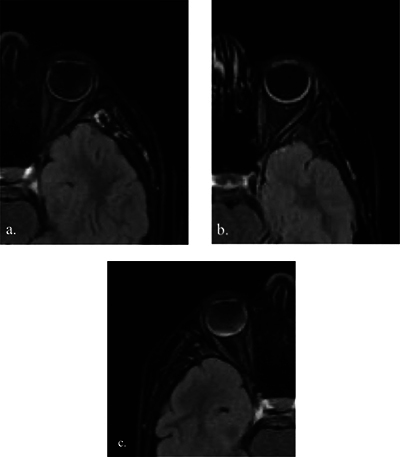

目的:对比增强FLAIR脂肪抑制(CE-FLAIR-FS)成像有可能提高葡萄膜疾病的诊断准确性,并最终提供更好的患者管理。本研究旨在确定 CE-FLAIR-FS 成像与对比增强 T1 加权成像(CE-T1WI)在评估儿童葡萄膜炎患者时的诊断价值。材料和方法:研究回顾性地纳入了21名接受全脑磁共振成像(MRI)(包括CE-FLAIR-FS和CE-T1WI)检查的葡萄膜炎患儿。我们评估了葡萄膜束对比度增强与增厚、玻璃体信号异常以及伴随的脑部异常。与 CE-T1WI 和 CE-FLAIR-FS 图像相比,葡萄膜增强强度被半定量地评估为轻度、中度和明显葡萄膜炎。结果显示全葡萄膜炎(61.9%)是最常见的解剖位置,其中大部分是特发性的(47.6%)。在 42 眼临床葡萄膜炎患者中,21 眼(50%)在 CE-FLAIR-FS 图像上观察到葡萄膜束增强,5 眼(11.9%)在 CE-T1WI 图像上观察到葡萄膜束增强。经检测,CE-FLAIR-FS 对泛葡萄膜炎的灵敏度相当高(80.8%)。CE-FLAIR-FS的受累眼数和增强程度更高(P < 0.001)。在评估葡萄膜炎的严重程度时,CE-FLAIR-FS 的分级明显高于 CE-T1WI,灵敏度更高(P < 0.001,Z:-4.347)。三名患者在 CE-FLAIR-FS 图像上出现玻璃体异常信号,但在 CE-T1WI 图像上却没有。结论CE-FLAIR-FS在诊断小儿葡萄膜炎、确定葡萄膜炎症的累及范围和严重程度以及指导适当的治疗方面发挥着重要作用。将其作为标准序列加入葡萄膜病变的常规核磁共振成像方案将大有裨益。

Objectives: Contrast-enhanced FLAIR fat-suppressed (CE-FLAIR-FS) imaging can potentially increase the diagnostic accuracy of uveal diseases and ultimately provide better patient management. This study aimed to determine the diagnostic value of CE-FLAIR-FS imaging versus contrast-enhanced T1-weighted imaging (CE-T1WI) in the assessment of pediatric patients with uveitis. Material and methods: Twenty-one children with uveitis who underwent whole brain magnetic resonance imaging (MRI), including CE-FLAIR-FS and CE-T1WI, were retrospectively included in the study. We evaluated the presence of uveal tract contrast enhancement with thickening, vitreous humor signal abnormality, and accompanying brain abnormalities. The uveal enhancement intensity was assessed semiquantitatively as mild, moderate, and marked uveitis compared to CE-T1WI and CE-FLAIR-FS images. Results: Panuveitis (61.9%) was the most frequent anatomic location, and most of them were idiopathic (47.6%). Of the 42 eyes with clinical uveitis, enhancement of the uveal tract was observed on CE-FLAIR-FS images in 21 eyes (50%), while in 5 eyes (11.9%) on CE-T1WI. The sensitivity of CE-FLAIR-FS in panuveitis was detected to be quite high (80.8%). The number of affected eyes and enhancement degree were found to be higher on CE-FLAIR-FS (p < 0.001). In assessing the severity of uveitis, CE-FLAIR-FS grades were significantly higher and more sensitive than CE-T1WI (p < 0.001, Z: -4.347). Three patients had vitreous abnormal signals on CE-FLAIR-FS images, but none on CE-T1WI. Conclusion: CE-FLAIR-FS plays a significant role in the diagnosis of pediatric uveitis, identifying the involvement and severity of the uveal inflammation and guiding the appropriate management. It would be beneficial to add it as a standard sequence to the routine MRI protocol for uveal pathologies.